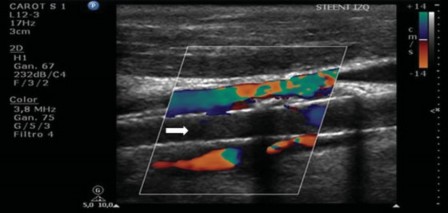

En modo color se debe documentar la permeabilidad del stent, la superficie del mismo y de la pared adyacente. Es preciso objetivar la existencia de zonas de aliasing color. Eso sucede debido a una pérdida dela laminaridad del flujo o bien a la existencia de zonas de turbulencia como consecuencia de una reducción de la luz vascular y, por lo tanto, es un hallazgo de importancia, ya que sería el sitio de interés para evaluar con el Doppler espectral en busca de estenosis (►Fig. 6). Frecuentemente, existen estenosis residuales de las arterias carótidas externas, secundarias al implante de la prótesis, sin implicancias patológicas relevantes.

Ecografía Doppler color (EDC) con ocupación de un tejido hipoecóico que prolifera hacia la luz (hiperplasia neointimal), con reducción de la luz vascular (estrella). El mapa color muestra el lumen disminuido con una zona de aliasing color (flecha).